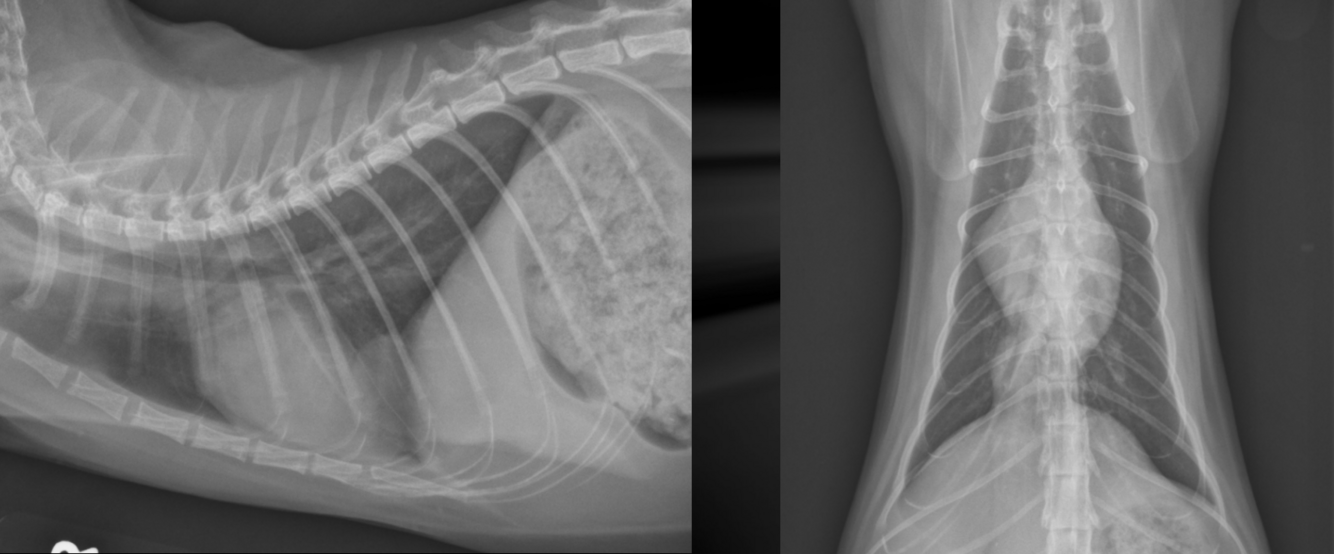

What is the chronicity of these rib fractures?

Left: acute

-displacement

-sharp margins

Right: chronic

-callus formation